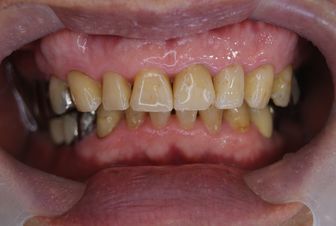

症例3

フィステル(瘻孔)があって、変色している症例。根管治療をすると、フィステルは消失。

レントゲン写真がこちら。根管治療&根管充填(この場合キャナルス&ガッターパーチャ)後。

で、漂泊してCR充填すればきれいに出来上がり。